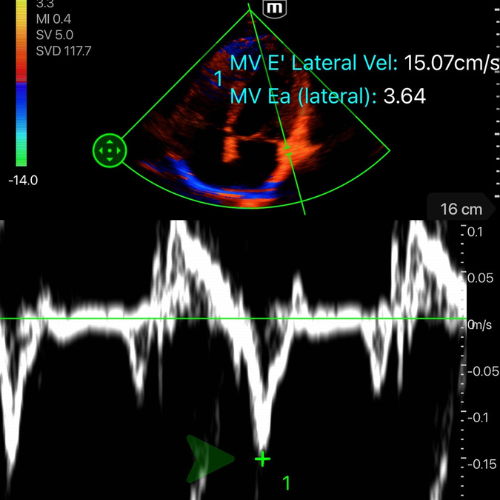

- En A4C, placer le curseur sur l’anneau mitral, en latéral

- Activer le mode Doppler tissulaire (TDI).

- Chercher la premiere onde négative apres le onde S' – c'est l'onde E’ (cf. vidéo/photo ci-dessous)

- Mesurer la vitesse maximale de E’. La machine fait le calcul du rapport pour vous.

-

E/E’ < 8, PRVG basses : le cœur tolérera un remplissage, et une hypovolémie est possible.

E/E’ > 14, PRVG hautes : tout apport hydrique risque d’aggraver la congestion ou de précipiter un œdème pulmonaire.

E/E’ 8–14, zone grise : l’interprétation dépend du contexte (tachycardie, sepsis, IC chronique, ventilation mécanique). Le chiffre seul ne suffit pas à guider la prise en charge.